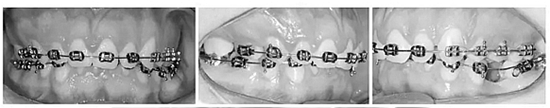

上下頜牙齒均粘貼0.022x0.028英寸的MBT托槽(3M / Abzil)并且使用0.014英寸的鎳鈦絲到0.020英寸的不銹鋼弓絲排齊、整平。

之后,在左上前磨牙之間植入種植釘,作為支抗,將右上部牙列向后移動至I類關(guān)系(Figure 6a-c)。原本想采用微種植釘體來矯正傾斜的咬合面,然而,微種植釘動度大,并且不能承受較大的負荷。取而代之的是,在左側(cè)上頜骨植入微鈦板作為支抗,用兩個懸臂(其用0.018x0.025英寸鈦-鉬絲制成)連接至鈦板上的兩個管并且系緊在弓絲上,以此壓低左側(cè)上頜后牙。此外,使用橫腭桿來避免左側(cè)后牙的頰傾(Figure 6d,e)。

在下頜從右下第二磨牙到尖牙以及從左下第二磨牙到第一磨牙使用片段弓,將0.018x0.025英寸的不銹鋼絲插入輔助管中并使用,直到下牙弓整平為止。在此之后,使用連續(xù)的弓絲來完成排齊整平。矯正上頜牙合平面后,在左側(cè)從微鈦板到下牙弓,使用頜間牽引伸長左下后牙。